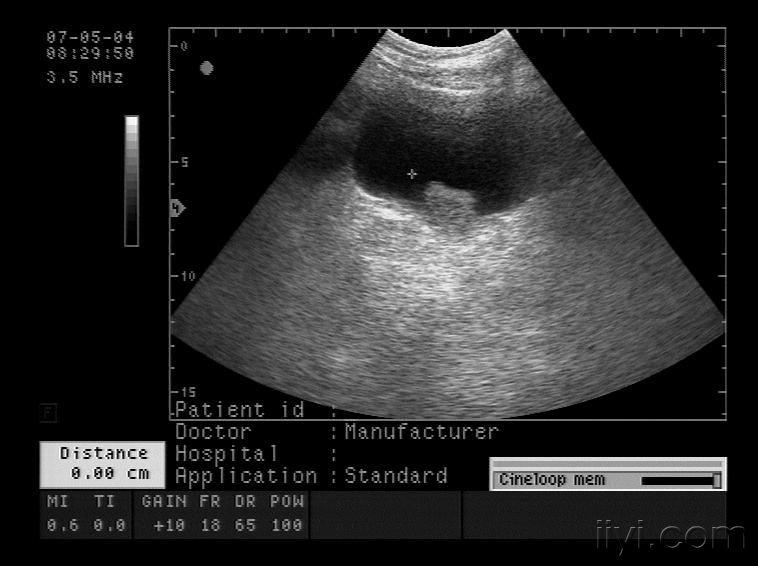

早期膀胱癌的彩超图

典型膀胱占位两例!(膀胱癌)

图片尺寸758x566